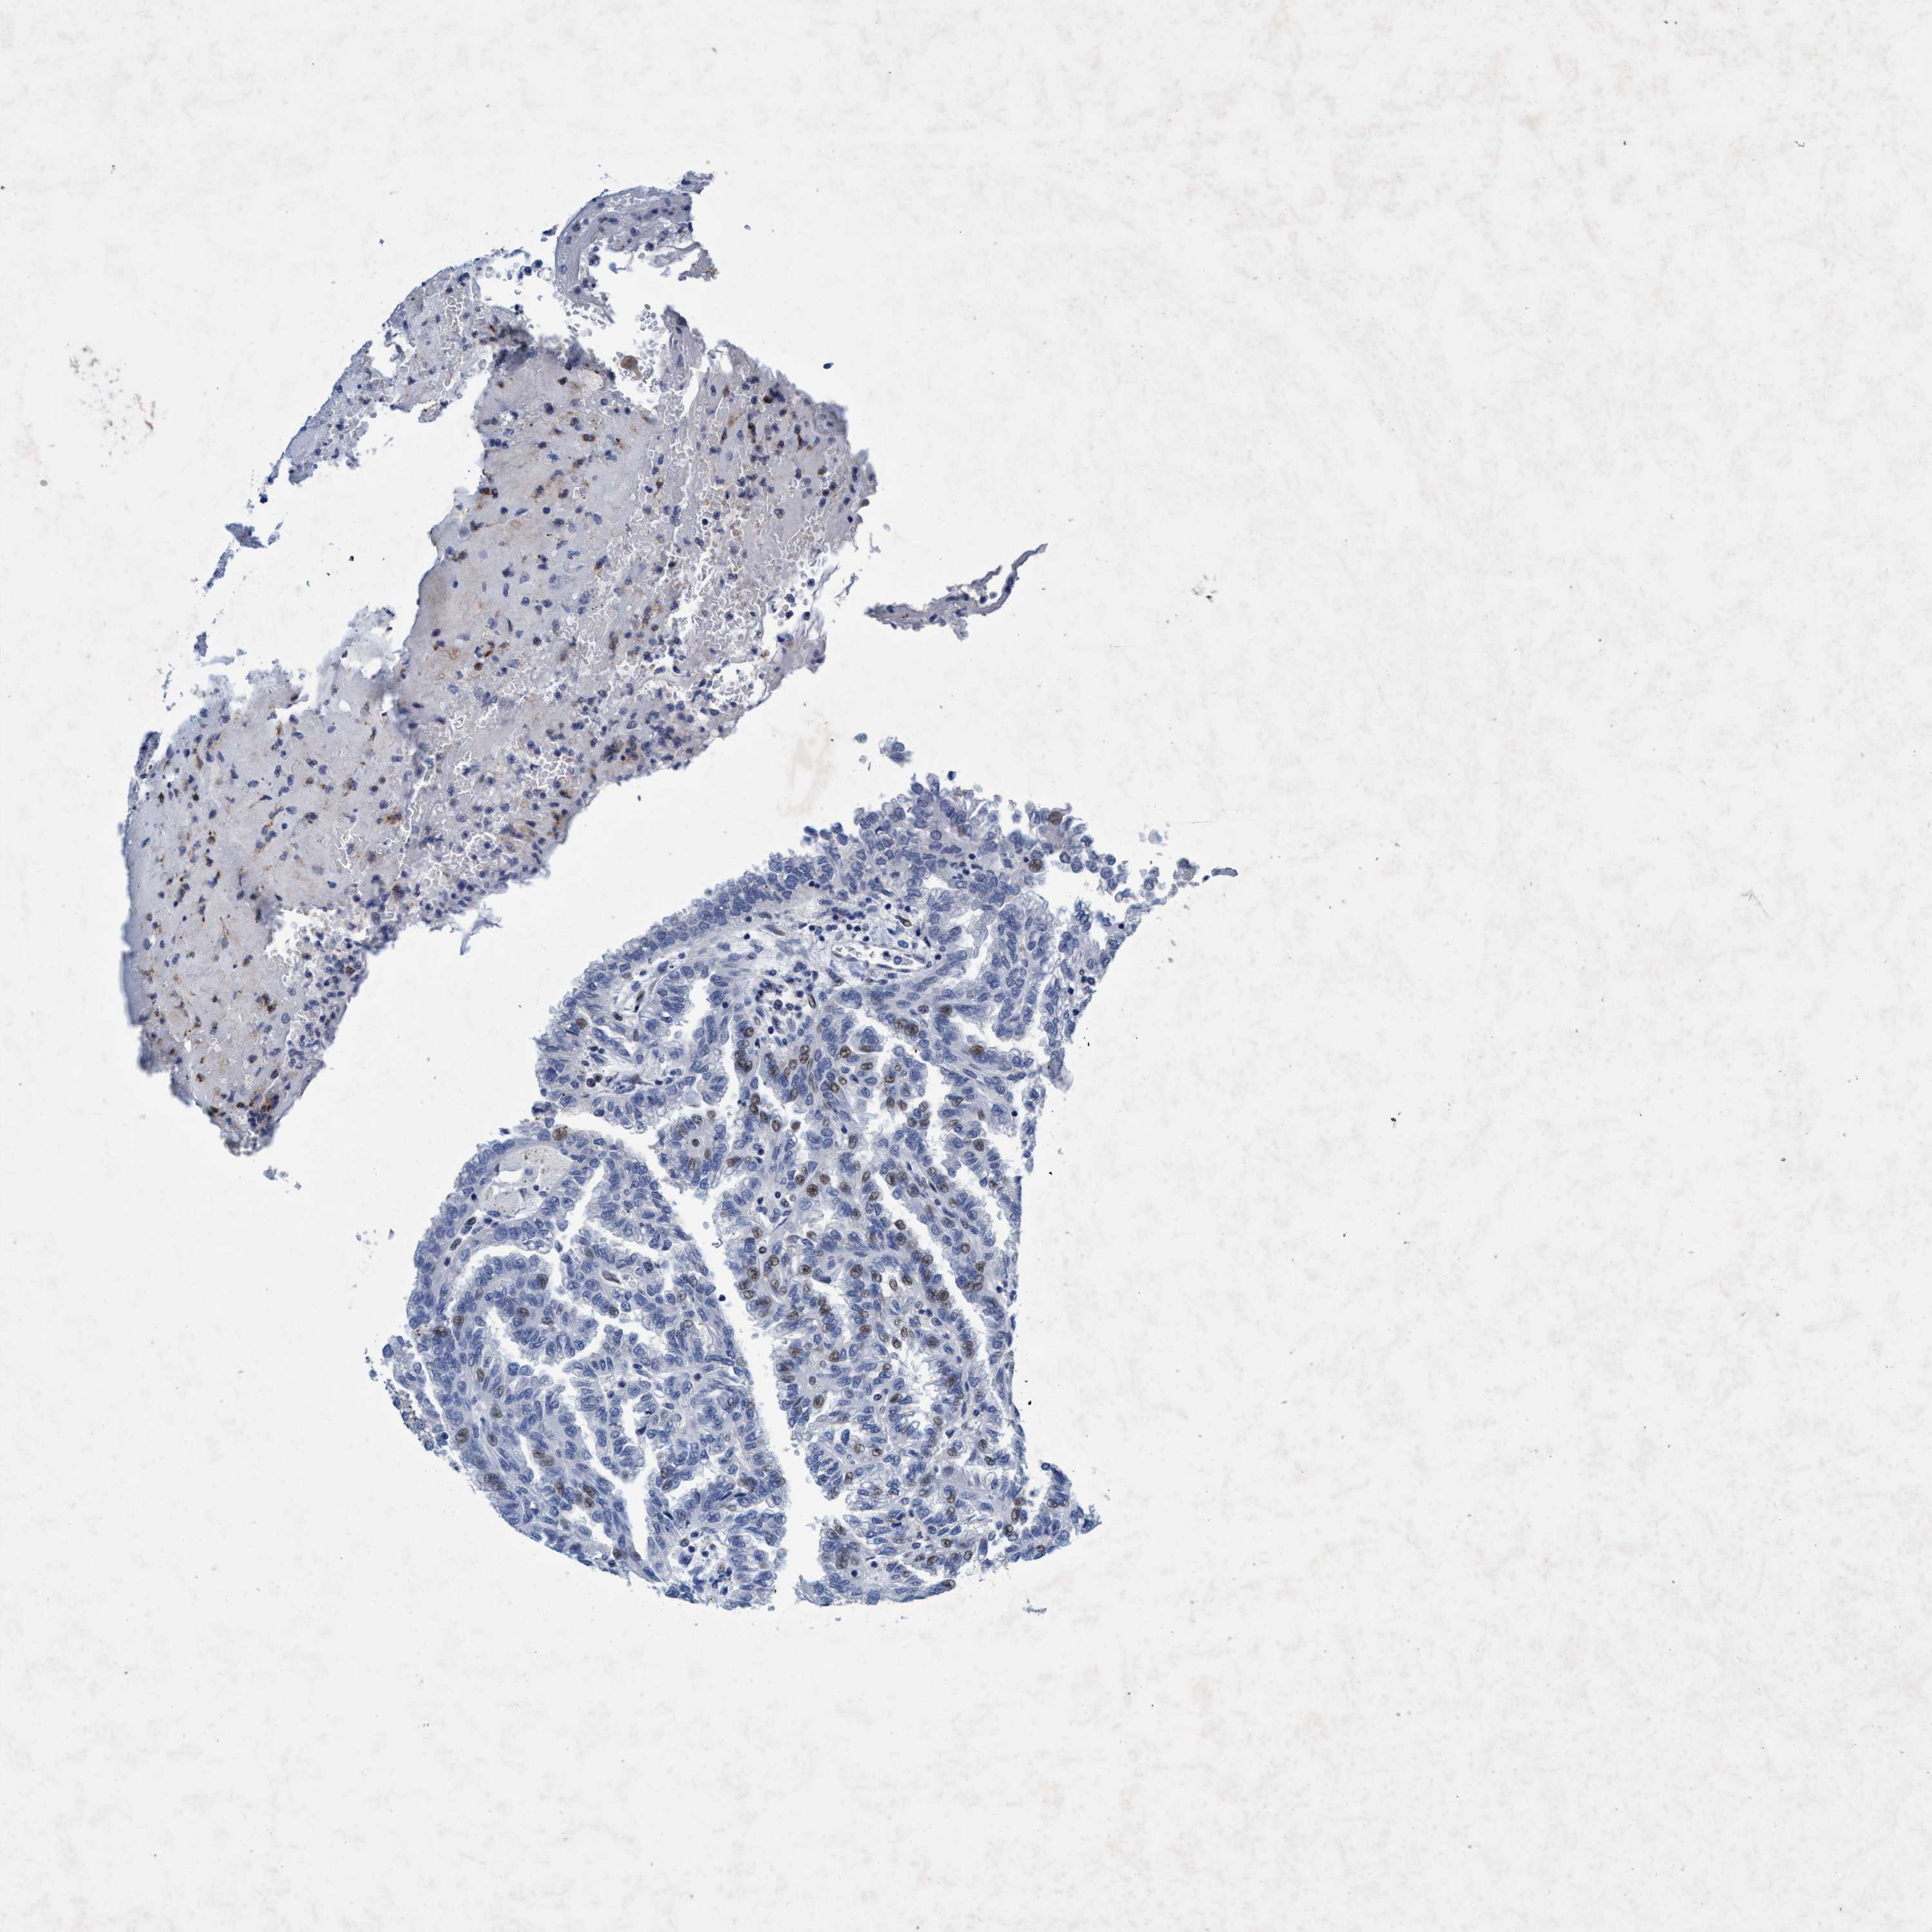

KIDNEY RENAL CLEAR CELL CARCINOMA (VALIDATION) - Interactive survival scatter ploti

& Survival analysisi

GRB14 is not prognostic in Kidney Renal Clear Cell Carcinoma (validation)

: 1.16

Average pTPM 1.9

Number of samples 100